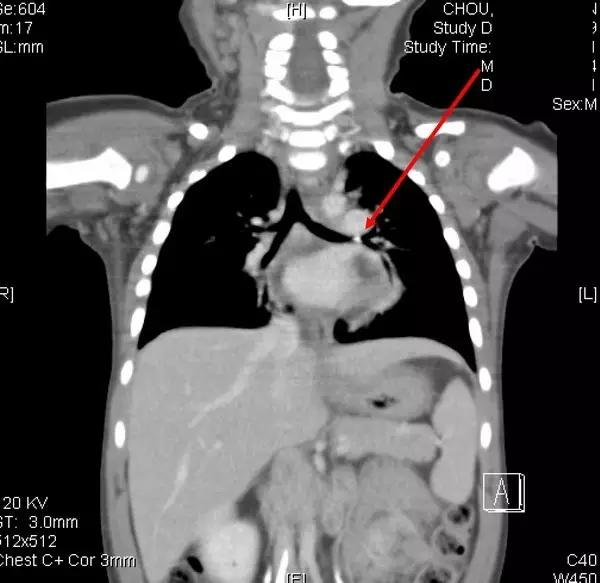

2岁的小光咳了2个月,原本以为是感冒,吃了不少感冒药,因为一直不会好,只好带到大医院,评估安排做进一步的检查。医师在检查之后,竟然用呼吸道内视镜从气管内夹出了一个小玩具车的小轮轴。仔细回想,爸爸妈妈才想到2个月前,小光把小玩具车放到嘴巴里,负责照顾的爷爷虽然手忙脚乱紧急抢下玩具车,却没有发现玩具车的小轮轴不见了。

“小东西进入气管”

虽然进入气管的小玩具小零件偶尔可见,事实上,常见进入气管的异物还是以食物居多,其中有三分之一是坚果类,尤其是花生。不管是那一种物品或食物,如果进入气管的异物完全阻塞呼吸道,会造成窒息,马上就有危险性,应在第一时间施行哈姆立克急救,如果是造成呼吸道的部分阻塞,可能出现哽住、作呕、咳嗽等症状,应尽速就医,以呼吸道内视镜取出異物。